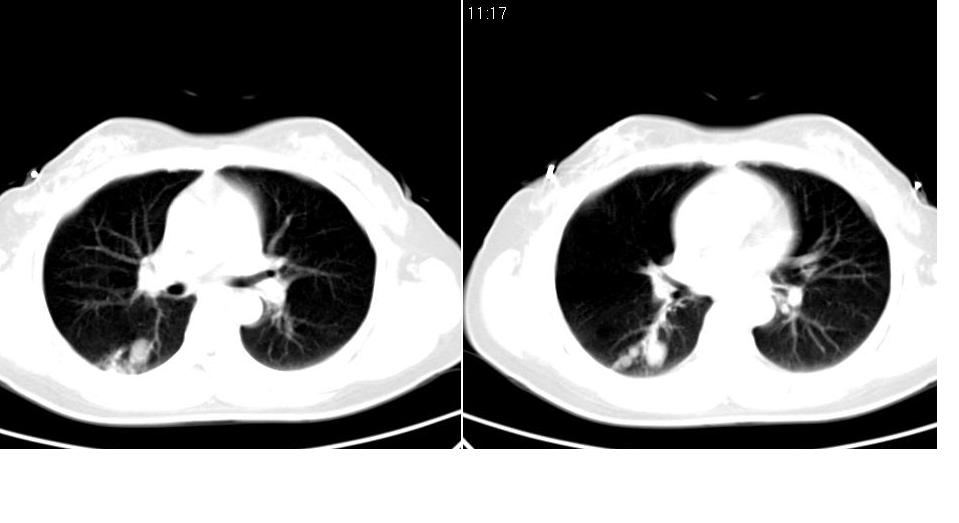

女 40岁,胸片体检发现右肺肿块,无任何症状。

考虑右肺下叶继发肺结核或炎症可能?

下叶背段多发性小腺泡结节,考虑结核。

考虑右肺下叶背段继发性肺结核。